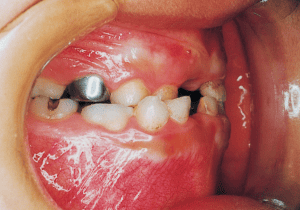

8 Beginning of 1st Phase 8-22-’88 7 years 1 month

9 After Phase 1 Treatment 8-21-’89 8 years 1 month

10 Perform lateral expansion of maxilla 7-4-’90 Midline is becoming deviated 9 years

11 During observation 4-1-’93 Midline deviation has become even greater 11 years 9 month

The Edgewise appliance was applied locally (8) and removed after 11 months (9). However, as the maxillary molar region gradually became crossbite, the maxillary arch was laterally expanded using a quad helix.